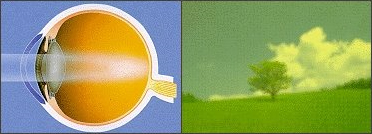

눈 속의 수정체 부분은 사물을 깨끗하고 또렷하게 볼 수 있게 하는데 가장 중요한 기능을 합니다.

이런 수정체가 젊었을 때는 맑다가 나이가 들면서 변화가 생기는 현상 중 하나인

뿌옇게 혼탁기가 증가되어 시력이 떨어지는 질환이 백내장입니다.

정상안 (물체가 선명하게 보인다)

정상안 (물체가 선명하게 보인다) -

백내장안 : 빛이 퍼진다 (물체가 흐릿하게 보인다)

백내장안 : 빛이 퍼진다 (물체가 흐릿하게 보인다)